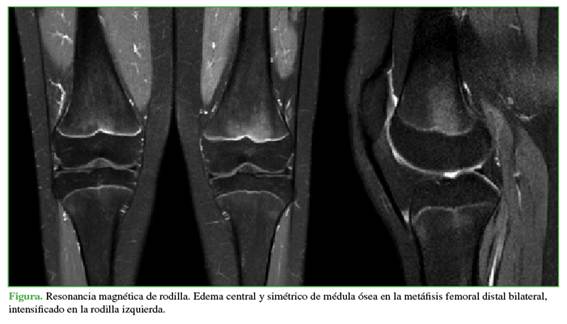

A los tres meses, acudió a la consulta de control, luego de ser evaluada por los médicos del Servicio de Reumatología, sin un diagnóstico específico. Continuaba con dolor intenso en la rodilla, y entregó una nueva RM realizada en forma particular, en la cual se visualizó claramente una lesión FOPE en el fémur distal, sin otros hallazgos patológicos (Figura). Por lo tanto, se diagnosticó lesión FOPE en la tibia proximal y el fémur distal de la rodilla izquierda. Se les explicó a la paciente y a la madre la baja prevalencia de este cuadro y se le ofreció un manejo con terapia física y analgésicos.

La paciente acudió con una resonancia magnética (RM) en la que se observaba, como único dato positivo, edema perifisario en el fémur distal y la tibia proximal izquierdos, sin ningún otro hallazgo de interés.